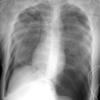

4 tension